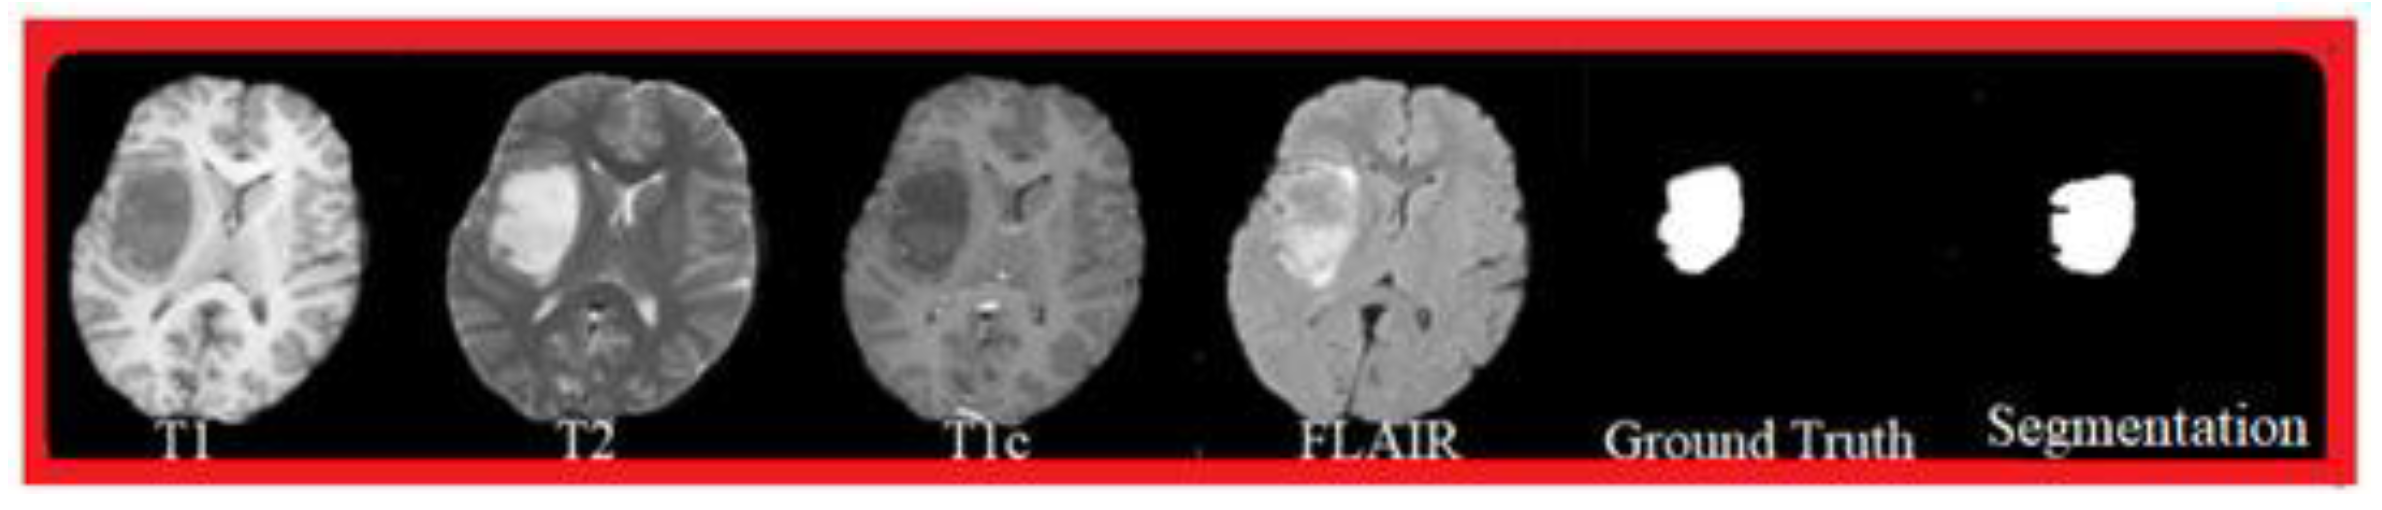

This study used longitudinal MRI data from 156 patients diagnosed with diffuse glioma. A total of 830 scan sequences were included, with 3–6 follow-up visits for each patient. All patients underwent routine clinical MRI without sedation. Each visit contained T1-weighted, contrast-enhanced T1, T2, and FLAIR scans. Images were collected from several hospitals using 1.5T or 3T scanners. As a result, the voxel size, slice thickness, and sequence settings varied across visits. Only cases with complete multi-sequence data and acceptable image quality were retained. Studies with motion artifacts or missing key sequences were removed. All imaging data were anonymized following institutional guidelines.

Figure 1. Segmentation results of the four models, presented by Dice scores and Hausdorff distances for the main tumor regions.

Preprints 191679 g001